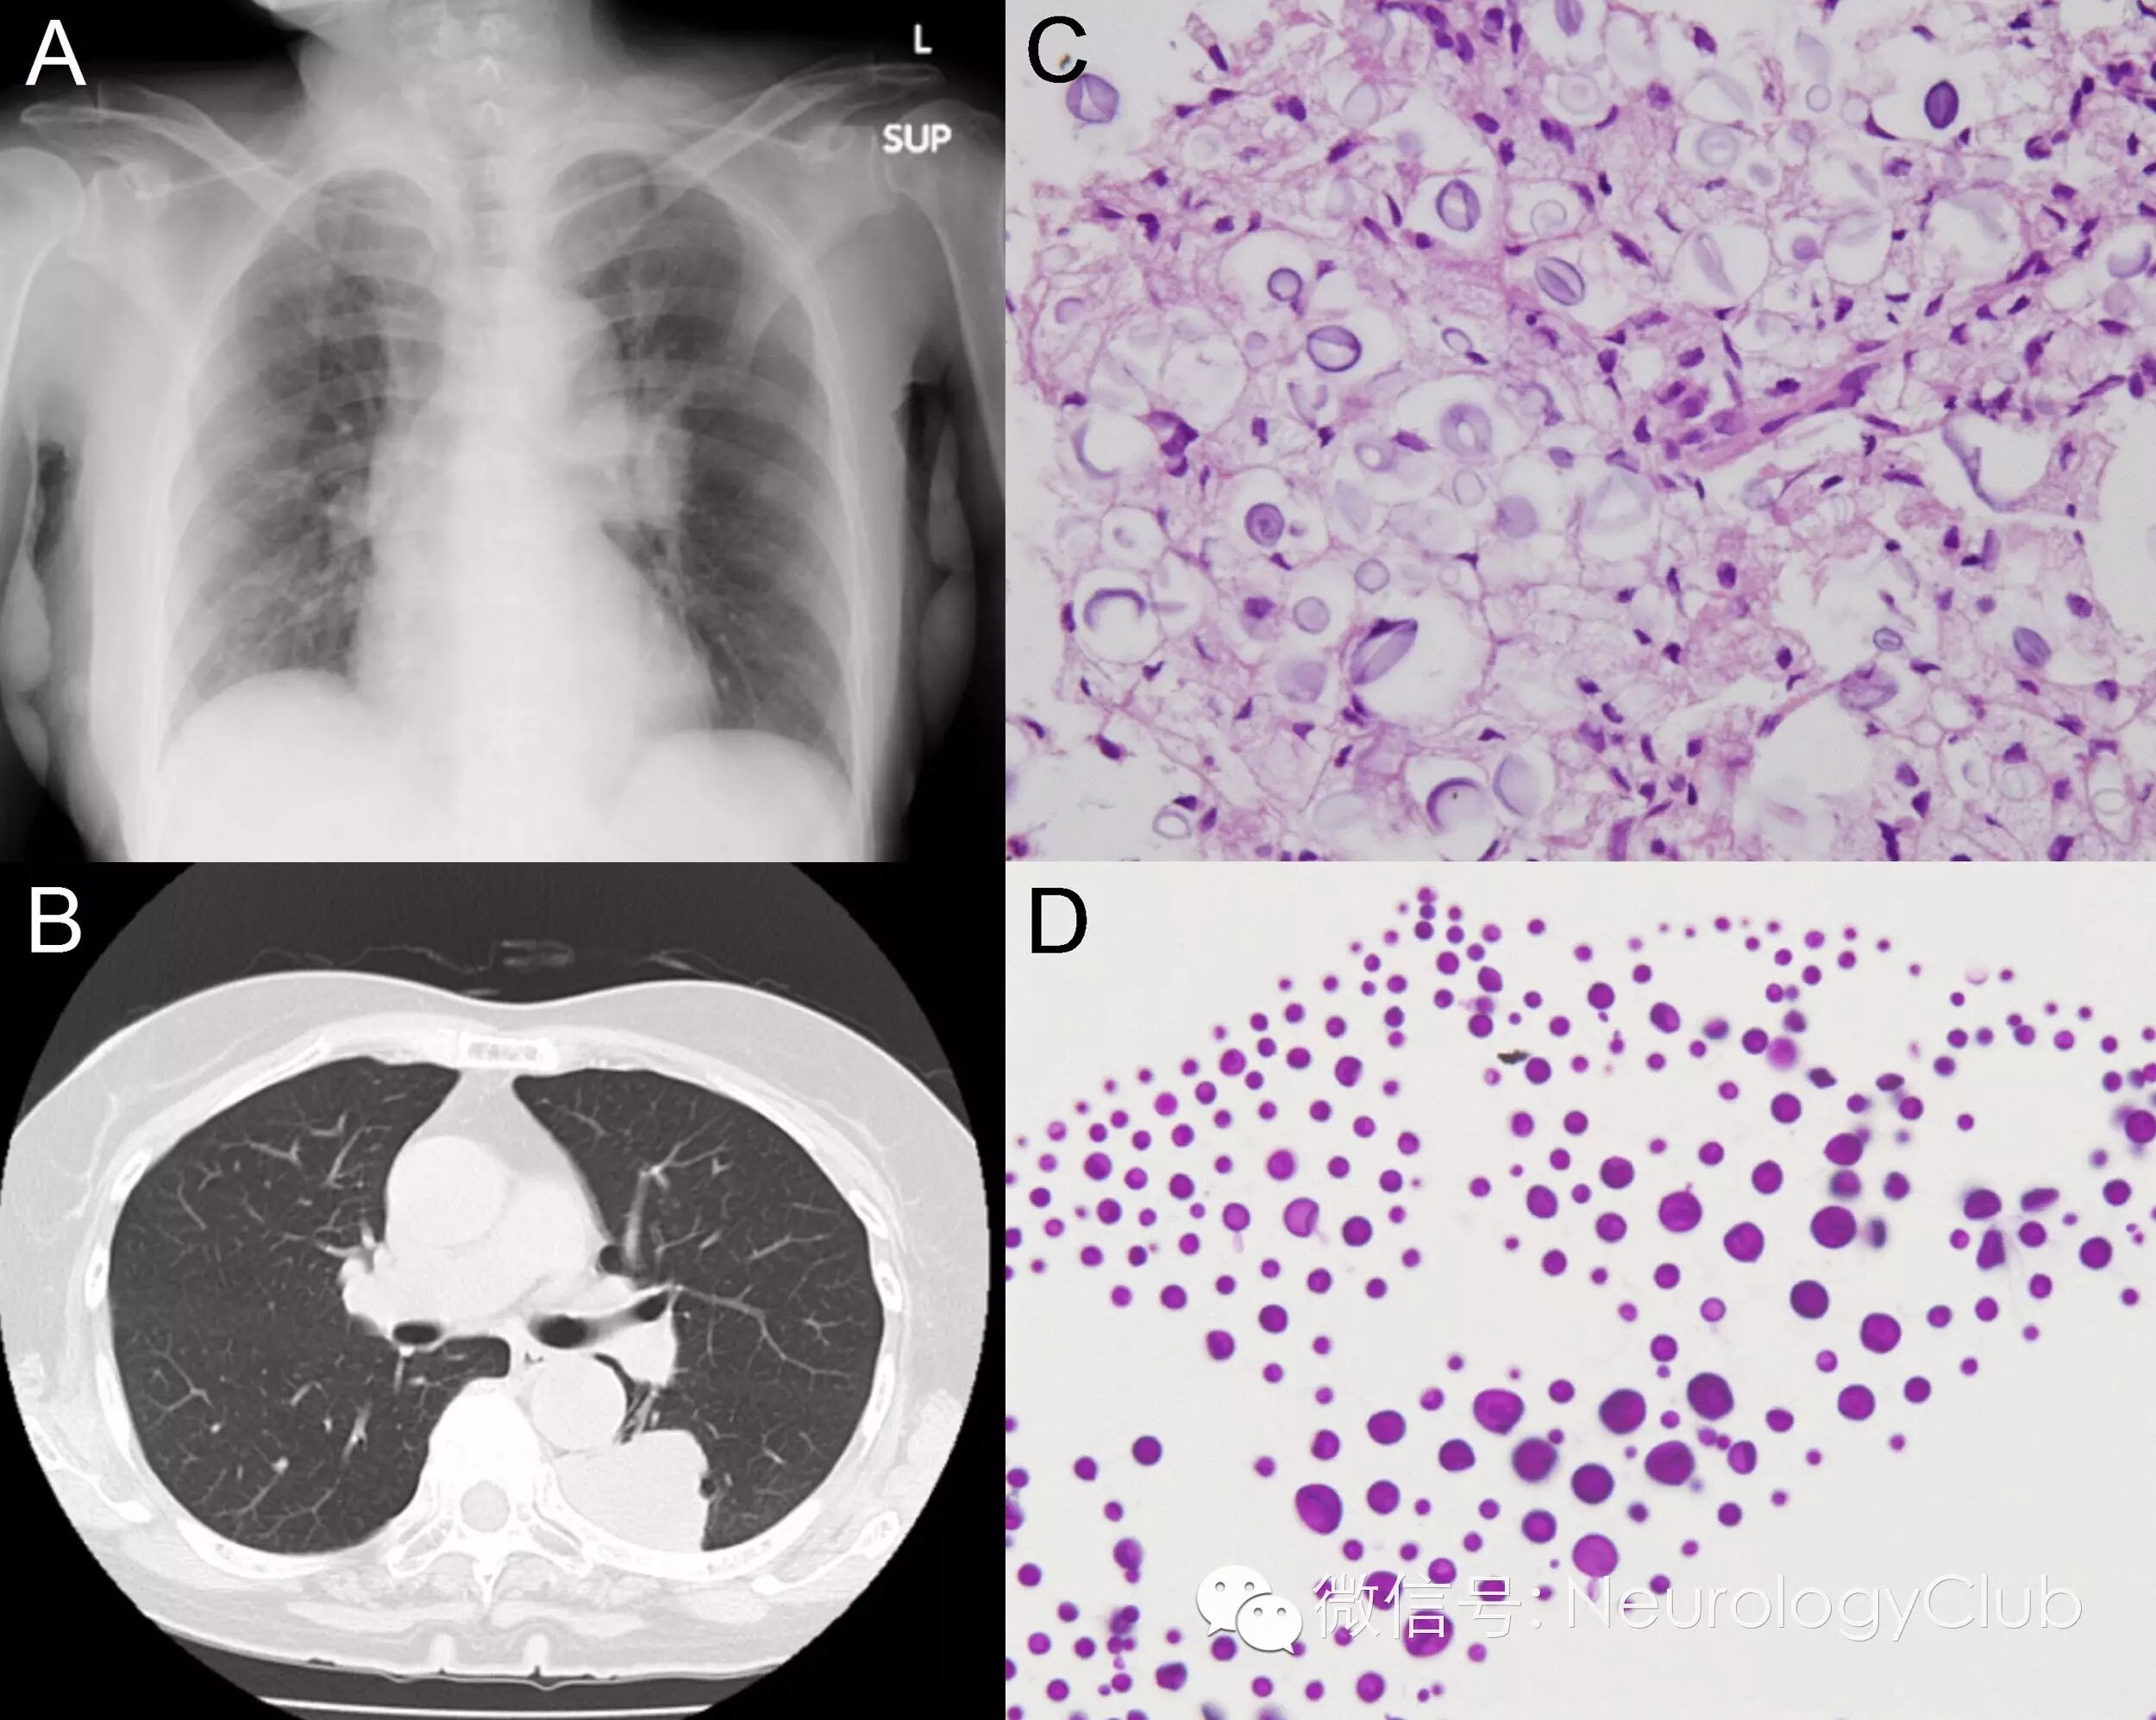

(图2:[A]胸片提示左下肺占位性病变;[B]CT显示肿块大小为4.5×3.8cm;[C]支气管镜活检组织提示微囊型新型隐球菌,HE×40;[D]脑脊液中可见酵母形态的新型隐球菌,过碘酸-希夫染色×40)

患者脑脊液可见许多酵母形态的新型隐球菌(图2)。血清和脑脊液隐球菌抗原阳性。血培养新型隐球菌阳性。患者诊断为中枢神经系统隐球菌病并开始两性霉素B脂质体静脉注射以及氟胞嘧啶鼻胃管给药治疗。随后行支气管镜活检,组织学标本中同样证实存在隐球菌(图2)。尽管开始抗真菌治疗,但患者症状仍不断加重。患者呼吸情况恶化可能与脑干功能障碍有关。患者在入院后3天上了呼吸机。静脉注射儿茶酚胺升血压。患者后出现弥散性血管内凝血,予以重组人可溶性血栓调节蛋白治疗。入院20天患者死亡。家属拒绝尸检。

本例患者最终诊断为肺和中枢神经系统隐球菌病。但其影像学改变并不典型。胸部CT可见一较大肿块,头颅MRI可见很小的环形强化提示隐球菌瘤伴周围水肿,后者在激素治疗后有所消退。上述影像学易误诊为肺癌伴脑转移

肺隐球菌病的临床表现和/或疾病发展因患者的免疫状态而异。免疫健全患者多表现为单个或多个肺部结节,直径通常<1cm。罕见>3cm的病灶,如出现难与肺癌区分。